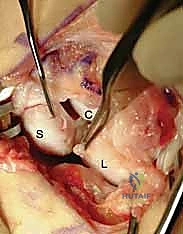

Primary Ligament Repair and Suture Anchor Fixation

With the joint anatomically reduced and held securely by an assistant (or temporarily pinned with a 0.045-inch K-wire across the SL joint), we proceed to the primary ligament repair. The scaphoid footprint is lightly decorticated with a small burr or curette to expose bleeding cancellous bone, optimizing the biological environment for ligament-to-bone healing.

Depending on the size of the scaphoid, one or two titanium or bio-composite micro-suture anchors (typically 1.5 mm to 2.0 mm in diameter) are inserted into the decorticated dorsal-proximal footprint of the scaphoid.

Micro-suture anchors are placed into the anatomic footprint on the scaphoid. The high-tensile strength sutures are then passed through the robust SLIL stump on the lunate using a horizontal mattress configuration.

The sutures from the anchors are passed through the lunate SLIL stump using a small, curved needle. We prefer a horizontal mattress configuration to maximize tissue capture and prevent suture pull-through. The sutures are then tied securely, drawing the ligament stump tightly against the bleeding scaphoid footprint.